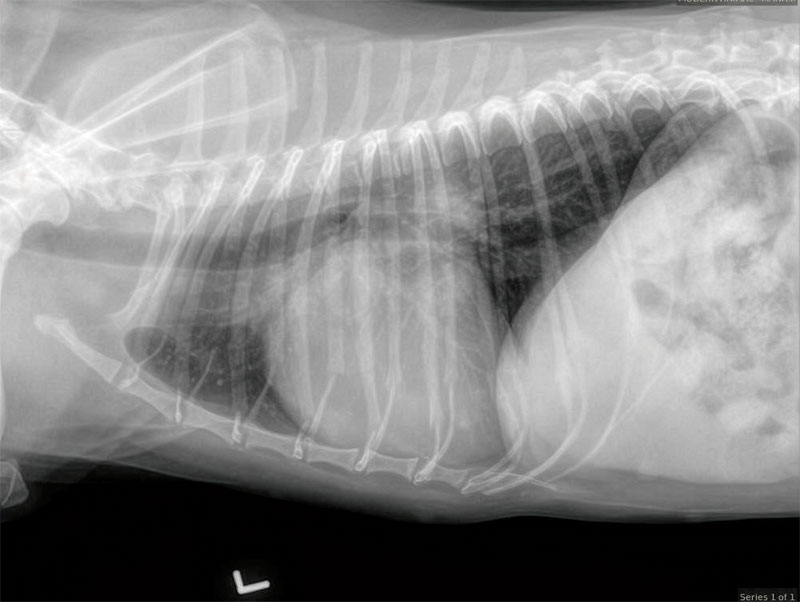

One study investigated myocardial Q10 concentrations in tissue samples from Cavalier King Charles spaniels (CKCS) diagnosed with myxomatous mitral valve disease (MMVD) in ACVIM stages B1, B2, and C, and compared them with a group of dogs with no evidence of heart disease. The main finding of the study was reduced concentrations of myocardial Q10 in CKCS diagnosed with MMVD in stage C compared to each of the other groups. The study concluded that depleted myocardial concentration of Q10 is associated with congestive heart failure (CHF) in CKCS diagnosed with MMVD.13